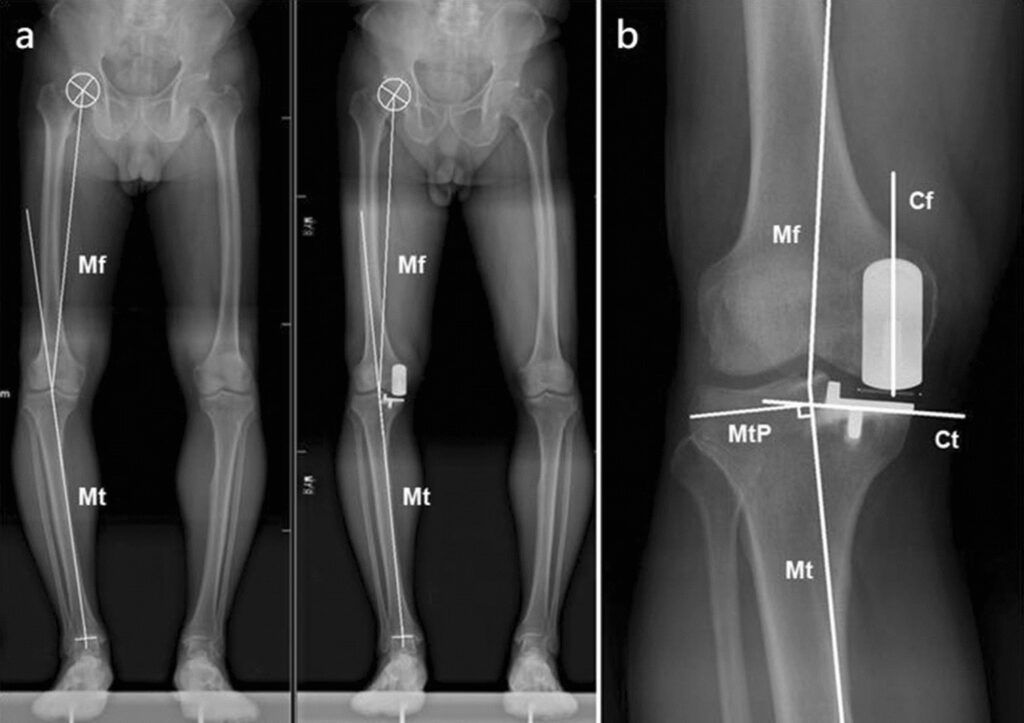

- Imaging studies, including X-rays to evaluate the position and integrity of the current implant, and to identify loosening or bone loss.

The new, revised knee implant is then carefully positioned and secured. Specialised implants, often with longer stems that anchor deeper into the femur and tibia, may be used to achieve better stability in cases of significant bone loss or loosening. The surgeon will then carefully balance the soft tissues, muscles, and ligaments around the new joint to ensure that it is stable throughout the range of motion and that the leg functions correctly when bending and straightening. Finally, the incision is closed with sutures or surgical staples, and a sterile dressing is applied.

Specialist Implants for Revision Surgery

Revision knee replacements often require the use of specialised implants designed to address the challenges posed by bone loss and implant loosening. These implants may feature:

- Longer Stems: These stems extend further into the femur and tibia, providing enhanced stability and fixation, particularly when the bone stock around the previous implant is compromised.

- Modular Components: Revision systems often have a range of sizes and shapes for different components, allowing the surgeon to precisely reconstruct the joint anatomy and restore proper alignment.

- Augments: Metal or bone graft materials can be attached to the implant components to fill in gaps caused by bone loss, creating a solid base for the new joint.

These advanced implants, along with meticulous surgical technique, are crucial for achieving successful outcomes in revision knee replacement surgery, restoring function and alleviating pain for patients with previously failed knee replacements.